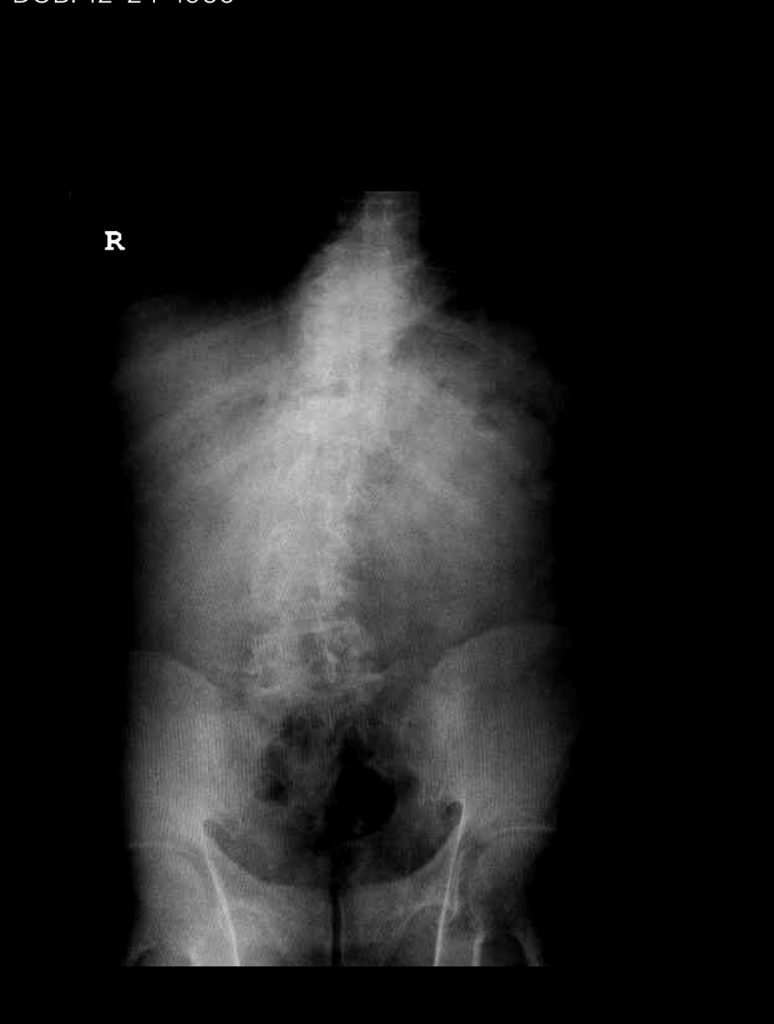

Figure 3. AP and lateral intraoperative fluoroscopic images demonstrating balanced pedicle screw placement.

We decided to perform a lumbar decompression L2-S1 with an instrumented fusion. The patient intraoperatively had severe thecal sac compression with severe facet arthropathy and thickened ligamentum flavum. The patient had bilateral L5 pars defects with a floating L5 lamina. Because of these factors and the patient’s age, it was decided to place screws (Fig. 3). The patient did well postoperatively with relief of his lower extremity pain and weakness.